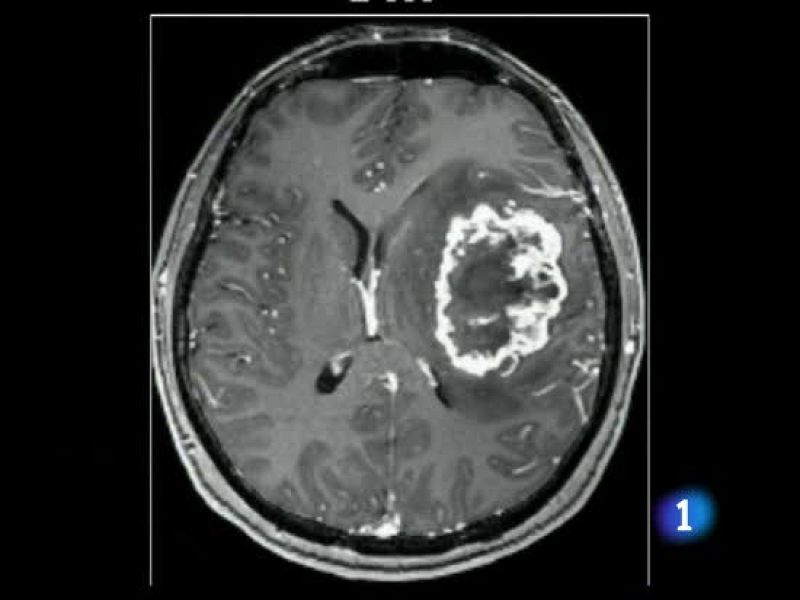

Se trata de una vacuna personalizada cuyo objetivo es evitar que se reproduzca el tumor alargando la vida de los enfermos. El ensayo lo ha puesto en marcha la Clínica Universitaria de Navarra.